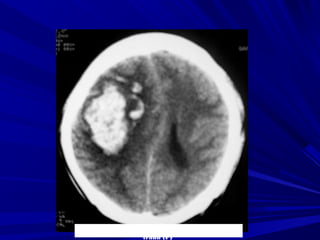

Phát hiện xuất huyếtPhát hiện xuất huyết

Xuất huyết là các vùng tăng đậm độ và có thể thấyXuất huyết là các vùng tăng đậm độ và có thể thấy

trong các bệnh lý:trong các bệnh lý:

Tụ máu ngoài màng cứng,Tụ máu ngoài màng cứng,

Tụ máu dưới màng cứngTụ máu dưới màng cứng

Xuất huyết màng nãoXuất huyết màng não

Xuất huyết não thấtXuất huyết não thất

Xuất huyết trong nãoXuất huyết trong não

Phân biệt hoá vôi và xuất huyết nhỏ vùng nhân nềnPhân biệt hoá vôi và xuất huyết nhỏ vùng nhân nền

Phân biệt xuất huyết cầu não với hình ảnh nhiễuPhân biệt xuất huyết cầu não với hình ảnh nhiễu